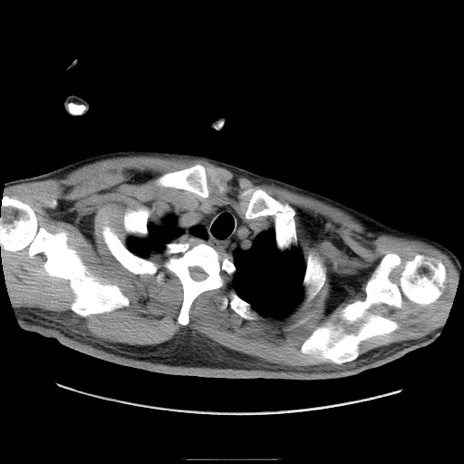

症例22(横断像)

【症例】50歳代男性

【主訴】腹痛

【現病歴】AVMからの被殻出血のため回復期リハ病棟入院中。 本日午後3時頃急に下腹部痛が出現した。

【既往歴】AVM、被殻出血、虫垂炎、高血圧

【身体所見】意識晴明、左半身不全麻痺、会話の理解は良好、36.5°C、腹部:膨隆、全体に板状硬、下腹部正中に圧痛点あり、反跳痛-、筋性防御不明、右下腹部にope scar

【データ】WBC 9400、CRP 0.06